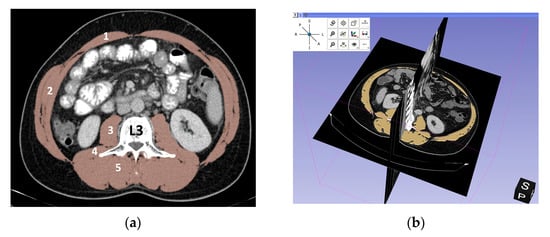

2.3. Assessment of L3-SMI (Skeletal Muscle Index)